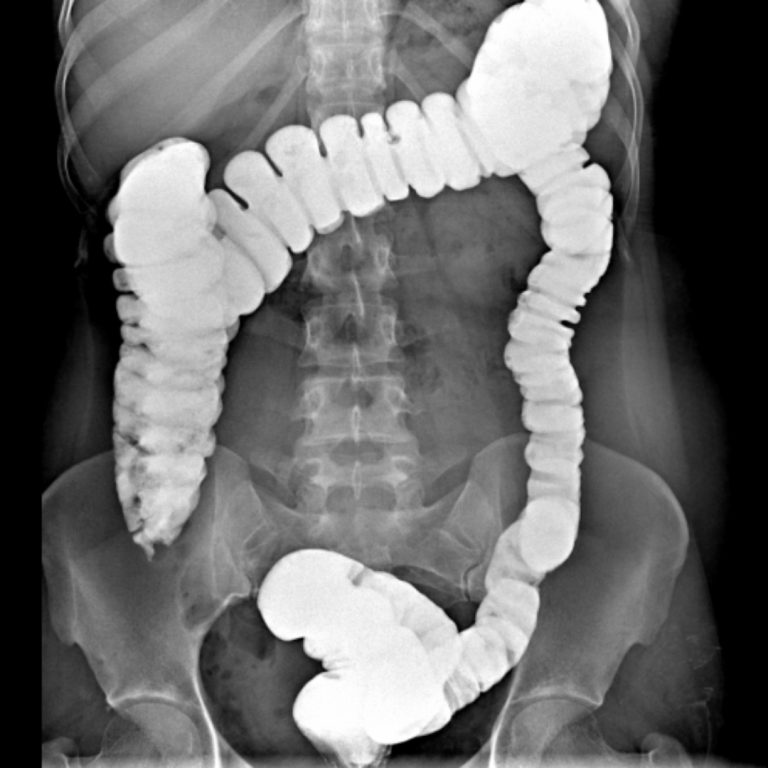

KOLON GRAFİLERİ

İki çeşit baryumlu kolon incelemesi vardır; tek kontrast ve çift kontrast. Kolon kanseri taramasında genellikle çift kontrastlı kolon tetkiki kullanılır.

- Tek Kontrastlı Kolon grafisi

Teknisyen makata bir tüp yerleştirir ve tüpün ucu baryum solüsyonunun olduğu torbaya bağlanır. Verilen baryum yavaşça kolonu sıvar. Bu şekilde kolon görünür hale gelir. Kolon baryum ile doldukça, dışkılama hissi duyulabilir. Baryum vermek için rektuma yerleştirilen tüpün ucunda küçük bir balon vardır. Tüp yerleştirildikten sonra baryum kaçışını engellemek için bu balon şişirilir. Tetkik esnasında masa üzerinde farklı yönlere dönülmesi istenebilir. Böylece verilen baryum tüm kolon segmentlerini doldurur ve kolonun farklı açılardan izlenmesine olanak sağlar. Filmler çekilirken nefesin tutulması istenir.

2- Çift Kontrastlı Kolon grafisi

Bu işlemin tek kontrastlı tetkikten en önemli farkı, kolonun hava ile doldurulmasıdır. Böylece daha kaliteli görüntü elde edilir. Polip gibi daha küçük lezyonlar rahatlıkla seçilebilir. Kolon tetkiki 20-30 dakikada tamamlanmakla birlikte, nadir durumlarda 45 dakikaya kadar çıkabilir. Bu tetkik karında hafif kramplara neden olabilir. Tetkikin bitimi ile şikâyetler sonlanır. Tetkik bitince rektuma yerleştirilen tüp çıkarılır ve kolonun boşaltılması istenir. Tetkiki takip eden birkaç gün dışkı, içeride kalan baryuma bağlı olarak beyaz, gri veya pembe görünümde olabilir. Geride kalan baryum kabızlığa neden olabileceğinden bol miktarda su içilmesi tavsiye olunur.

Rektal yoldan verilen kontrast madde takıntısız çekuma ulaşmış olup ilioçekal bileşke serbesttir. Apendiks vizüalize olmuştur ve normal görünümdedir. Rektum posterior konturu muntazamdır. Presakral mesafe açıktır. Kolon boyunca belirgin haustrasyon artışı mevcuttur. Sigmoid kolon hafif elonge görünümdedir. Kolon lümeninde doluş defekti lehine bulgu saptanmamıştır. Evakuasyon fazında sağ kolon ve hafif sigmoid kolon içinde remnant kontrast madde kalmıştır. Diğer segmentlerdeki kontrast maddenin bulunmaması mukozanın ödemli olabileceğini düşündürmektedir. Çift kontrastlı grafiler ve sağ kolondaki kontrast maddesinin fragmane olduğu dikkati çekmektedir. Bulgular irritable kolonla uyumlu bulunmuştur.